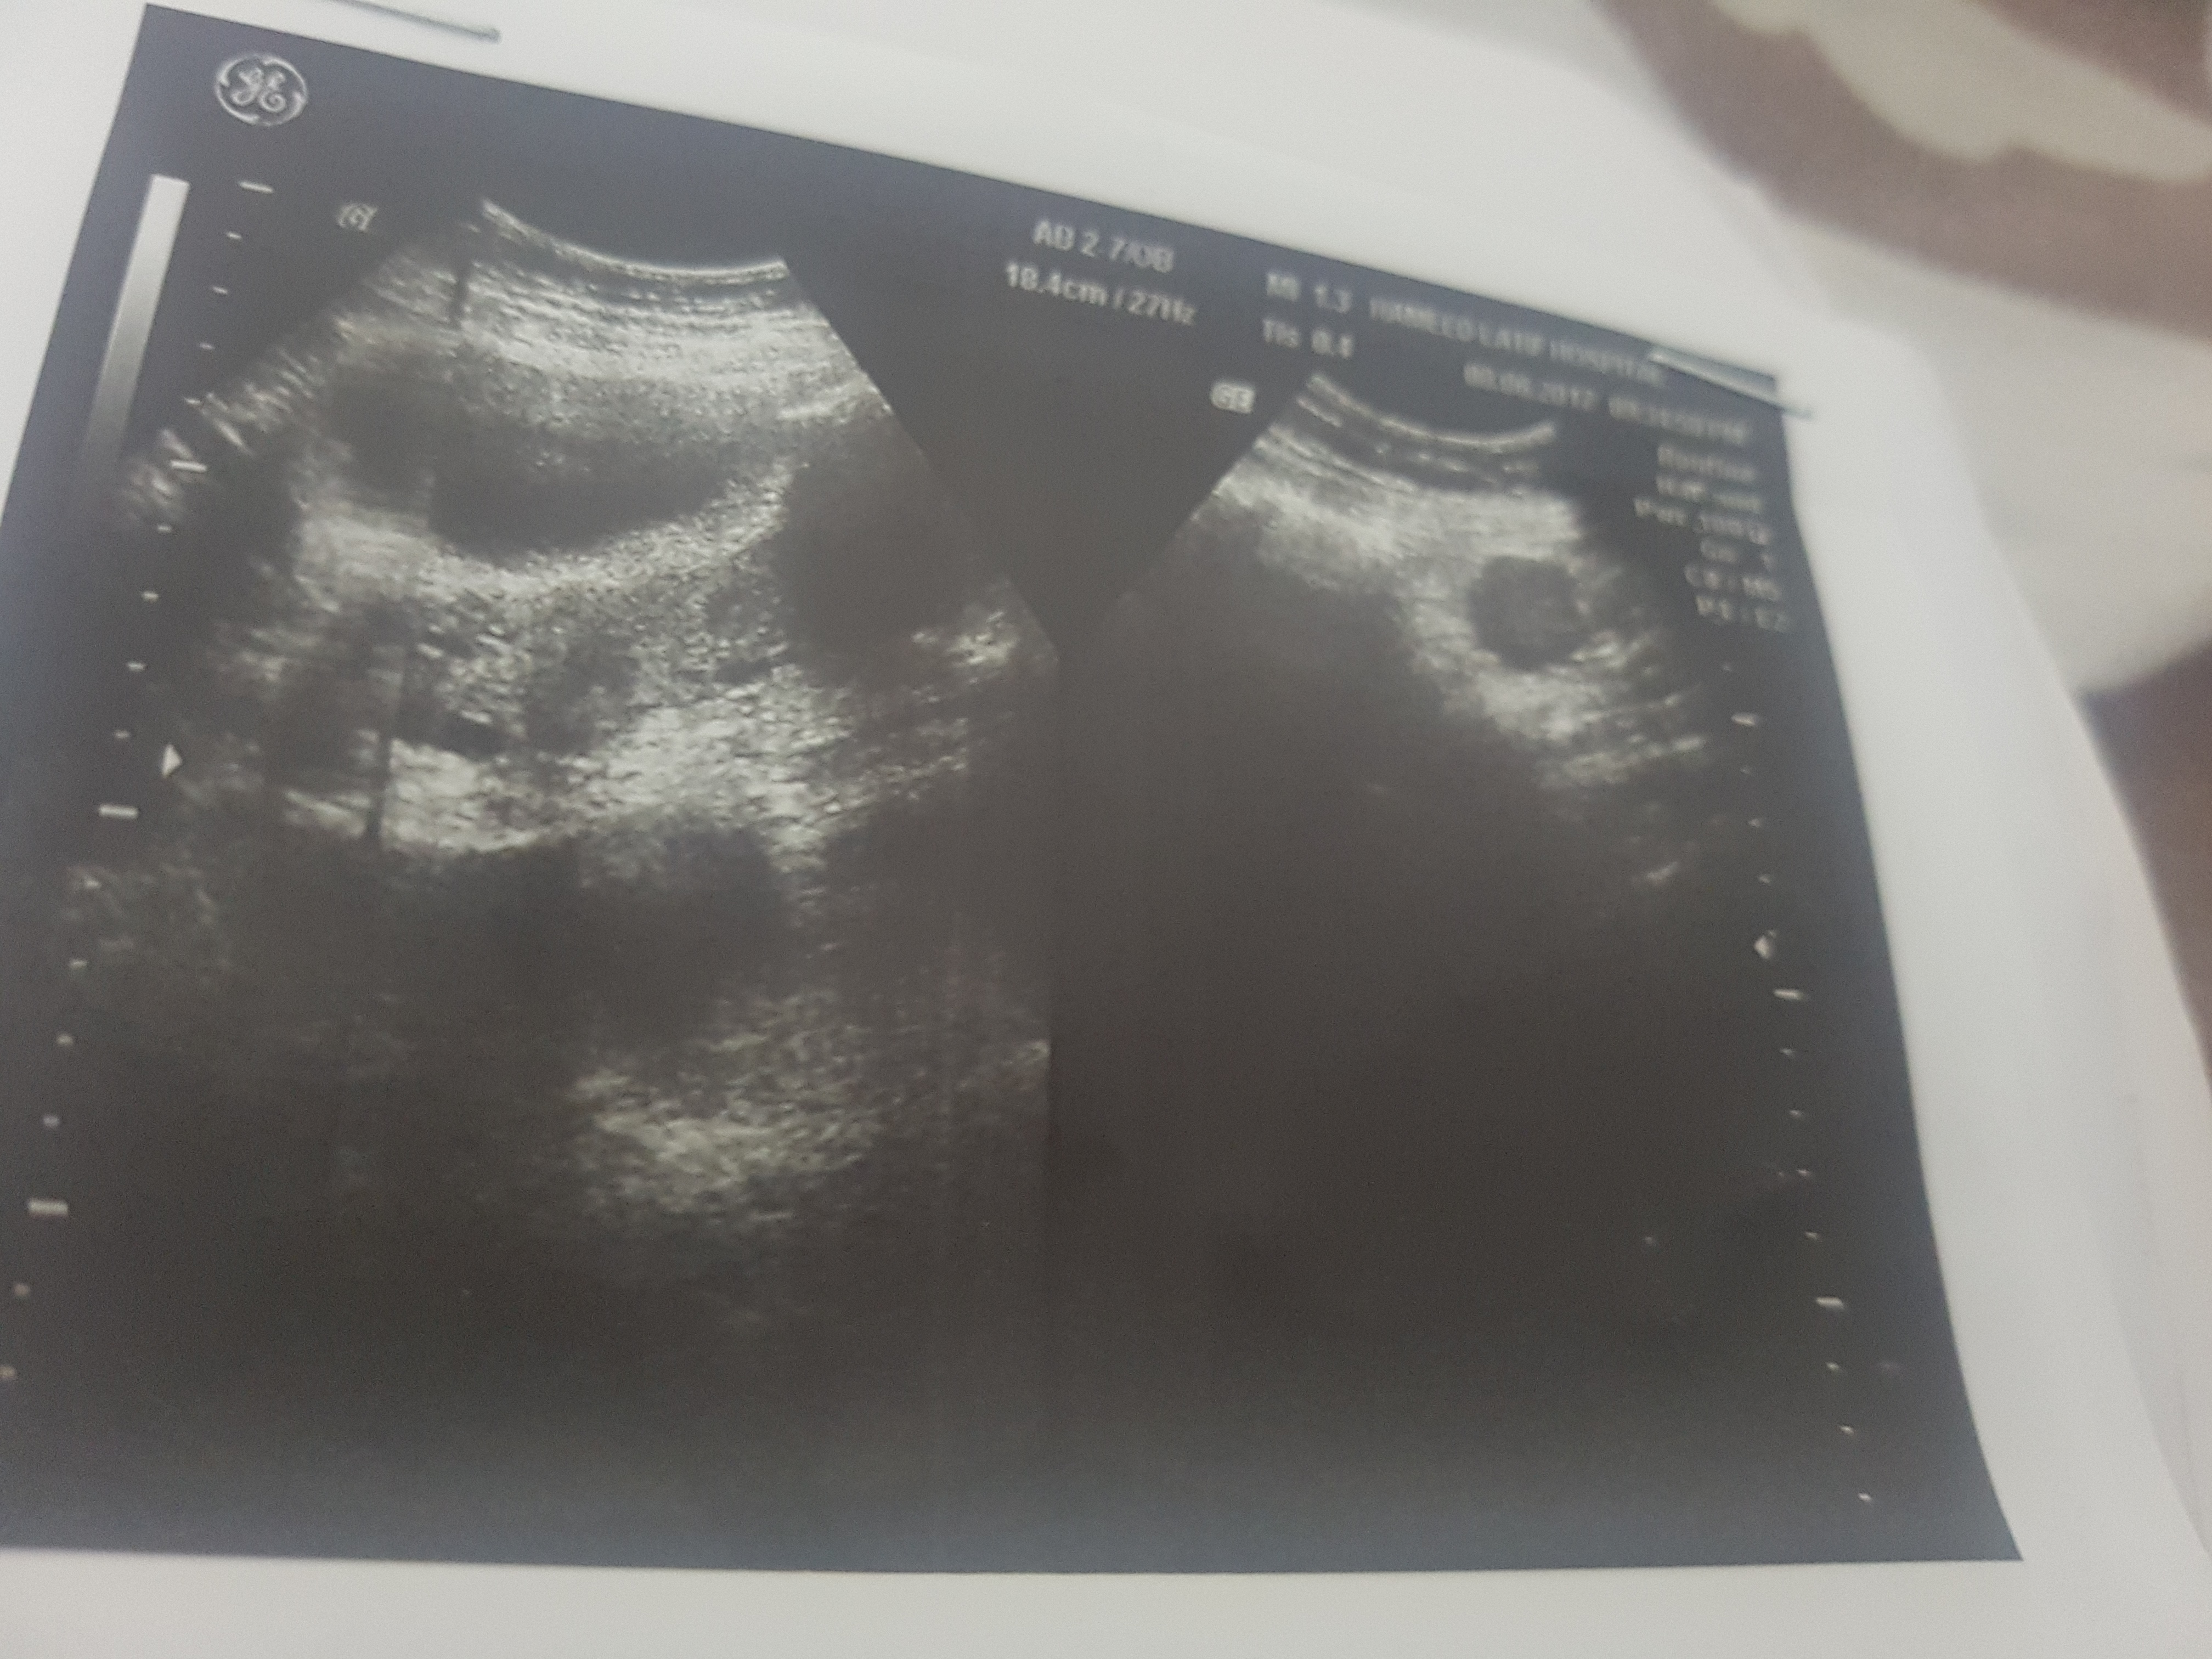

these r my ultrasound report should i go for surgery?? ak br mai ny expect kia ha par result was explusion in 24 weeks plzz guide me im not conceiving again

ak dafa mai ny conceive kia tha 24 weeks mai explusion 6 mnths phly hwa tha us k bd abi tk concieve nai says k take 1 more chance.. surgery k bd conpliction hti ha conceive krny mai